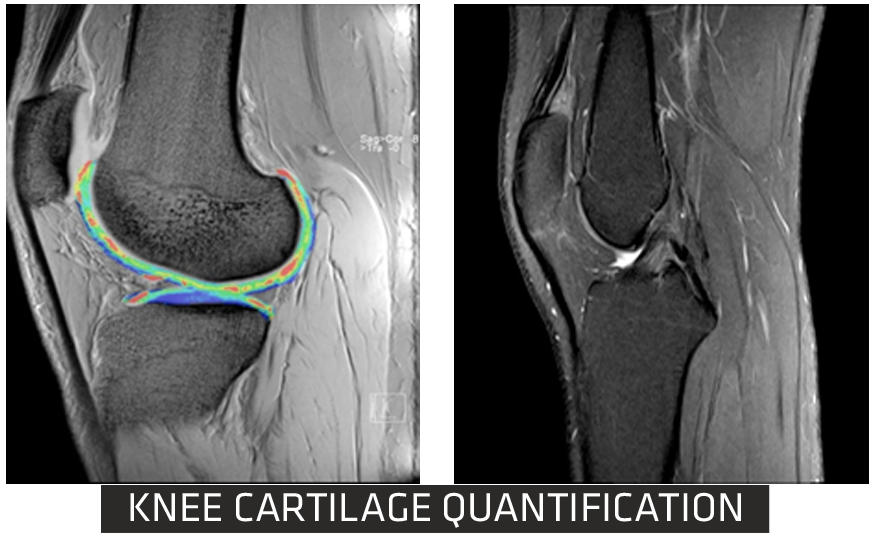

With advancements in MSK sequences, RF coils, computing technology and optimized magnet homogeneity, Clarity delivers high resolution musculoskeletal(MSK) images. This imaging technique enables you to image bone, joint and muscular soft tissue with remarkable tissue contrast.

Cartilage Quantification provides quantitative assessment of cartilage composition to track the degradation of tissues in the early stages of multiple pathologies? within joints, which can't be detected by conventional imaging techniques. It allows for non-invasive measurement of collagen content.